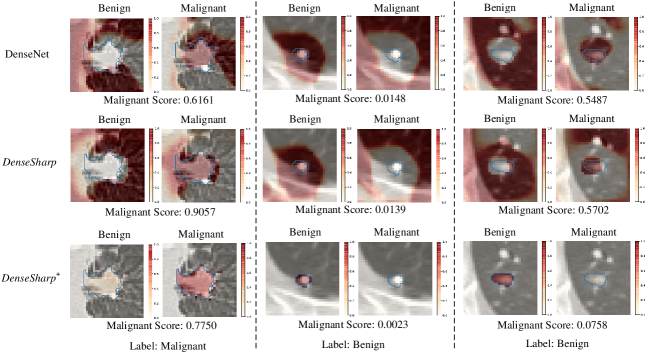

Deep learning111We refer to deep learning in a narrow sense, i.e., applying CNNs directly on the medical image analysis problems. provides a strong alternative to learn representation from raw voxels (or pixels) in an end-to-end fashion. Convolutional neural networks (CNNs) have achieved great success in medical image analysis, though they are classifying voxels, rather than lesions. In other words, there is no guarantee that black-box CNNs correctly learn evidence from lesions, especially with limited supervision. We illustrate several failures in Appendix Fig. 0.A.2, by checking the Class Activation Maps (CAMs) [13] from a 3D DenseNet [4, 12] on lung nodule malignancy classification. These failures make the predictions given by CNNs unreliable. In contrast, Radiomics analysis is more controllable and transparent for users than black-box deep learning.

Moreover, thanks to the explicit modeling, only voxels in lesions are counted, the visual saliency maps produced by the is highly calibrated with the nodules. Please refer to Appendix Fig. 0.A.3 for illustration.